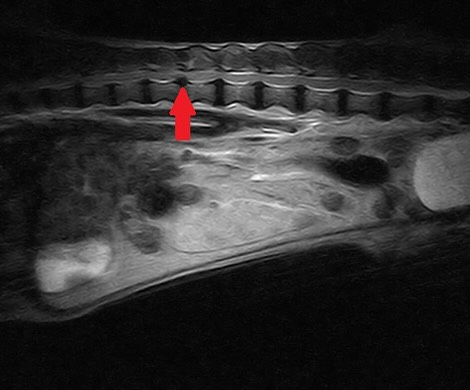

椎間板ヘルニアで手術を行ったワンちゃんです。MRIで腰の椎間板ヘルニアと確定診断を行い、手術を行いま..

椎間板ヘルニアで手術を行ったワンちゃんです。MRIで腰の椎間板ヘルニアと確定診断を行い、手術を行いました。手術前は歩けなかったのですが、手術後1週間で徐々に良くなり、なんとか歩行できています。2ヶ月間..